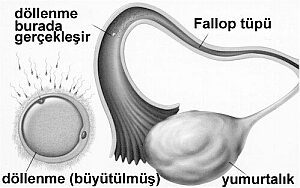

Şuana kadar herhangi bir değişiklik farketmesenizde gebeliğin en kritik olayı olan döllenme bu hafta içinde gerçekleşir. Yumurta hücresi yumurtalıklardan atılır ve tüp boyunca rahme doğru ilerlerken sperm hücreleri ile karşılaşıp, döllenme olayını gerçekleştirir. Döllenmenin ardından henüz ufacık bir hücre olan bebeğin hücreleri hızla çoğalmaya başlar. Bu sırada da rahmin içine...

Regl evresinin başlangıcından itibaren 7 ila 14. gün arasındaki zamanda döllenme yani embriyo meydana gelmemiştir. Muhtemel gebelik için gerekli olan yumurta hücresinin büyümesi bu evrede devam etmektedir. Bu hafta sonunda gelişen yumurta hücresi ovulasyon adı verilen yumurtlama olayı ile oluştuğu yandaki tüpe aktarılır. Gebelik oluşması için önemli olan durumlardan biride...